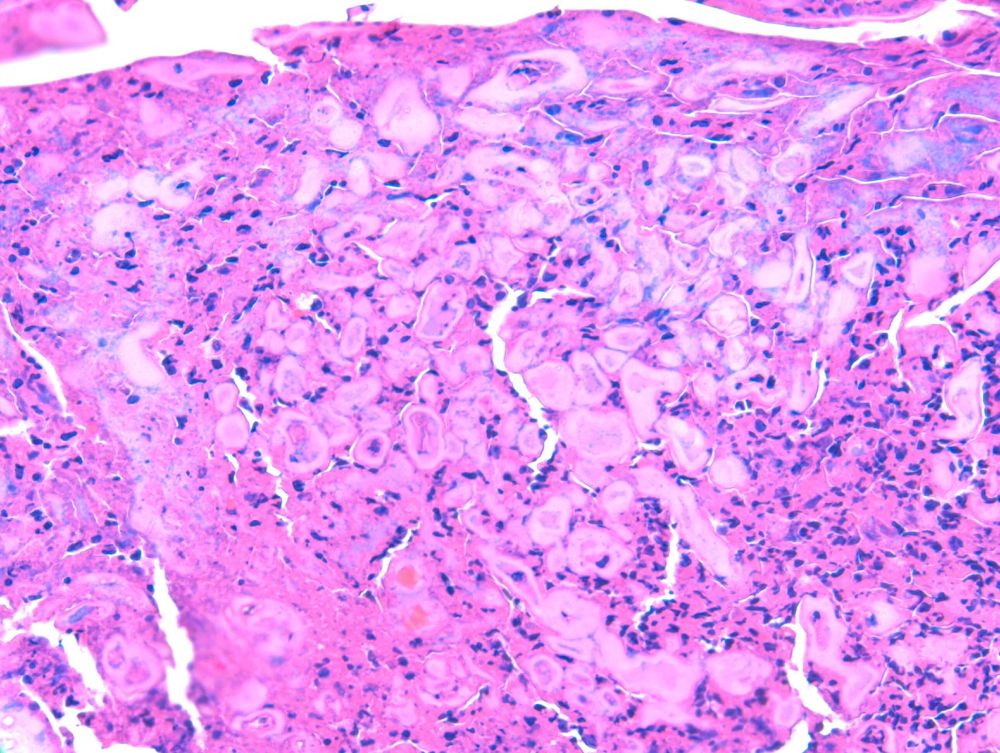

RAC9306. M80s. Nose. SCC. #dermpath @rishiagrawal.bsky.social

RAC9302 M80s Presternum. ?SCC #Dermpath @rishiagrawal.bsky.social